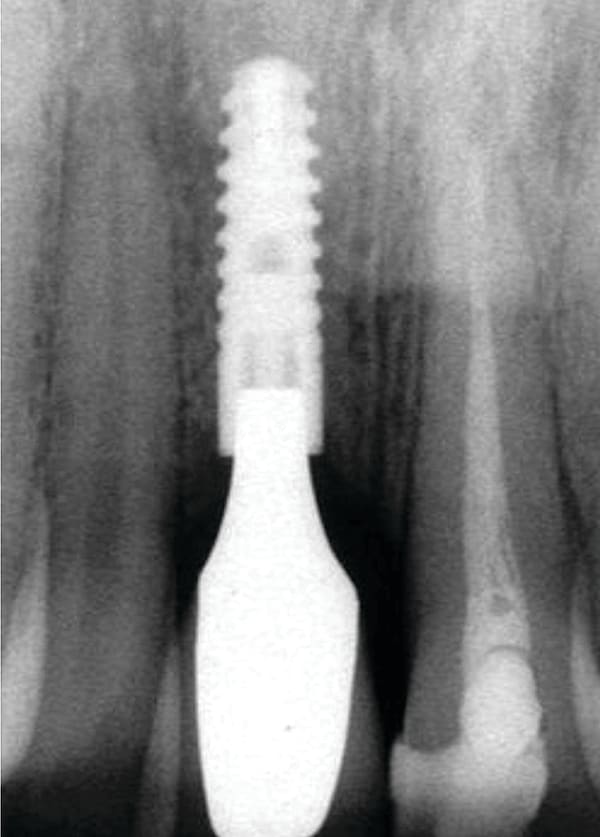

The esthetic advantage of a platform-switched implant with a customized zirconia abutment is demonstrated in the clinical case of a 24-year-old woman who received a provisional restoration after implant surgery (Figure 15 through Figure 19). The provisional was over-contoured, putting too much pressure on the peri-implant soft tissue. A soft-tissue necrosis developed due to inadequate blood supply to the affected area. The prosthodontist was able to save the case by using a customized zirconia abutment and a zirconia crown.